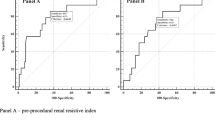

Best RRI cutoff value to predict WRF

In the ROC curve analysis, when WRF was considered, the RRI at baseline showed an AUC of 0.85 (95% CI, 0.77–0.92) (Fig. 1). The AUC was even greater when the RRI after coronary angiography was considered (0.89; 95% CI, 0.83–0.96). Both the baseline RRI and that after angiography showed an AUC greater than that observed for the baseline GFR-EPI (0.75). The best cutoff value of the RRI (70) was both at baseline and after coronary angiography with a sensitivity that increased (from 79 to 93%) and a specificity that decreased (from 93 to 82%). The proportion of patients with RRI values ≥ 70 increased after coronary angiography in both patients with and without WRF (Fig. 2).

This study demonstrated the greater role of assessing renal resistance rather than estimating the GFR in defining an increased risk of WRF after the administration of contrast media. In our series, at baseline, both a greater RRI and a worse GFR were associated with WRF; however, in the multivariate regression analysis, only the RRI remained associated with WRF. Moreover, in the ROC curve analyses, the RRI showed greater predictive accuracy than GFR.

The cutoff value of 70 as a marker of increased risk of WRF is consistent with previous studies. In patients with CHF, an RRI ≥ 70 is associated with a greater risk of WRF. In patients affected by CKD, the RRI is associated with irreversible damage [9] and a greater risk of CKD progression [25] and mortality [26]. Consequently, both before and after coronary angiography, an RRI ≥ 70 indicates a critical increase in renal resistance, which can predispose to WRF. Kajal et al. have observed similar data [27]. In their study, 115 patients undergoing on-pump coronary artery bypass graft surgery were observed. In this series, an RRI ≥ 70 before or during surgery allowed the differentiation of patients at risk of WRF in the postoperative period from those who are not.

This study demonstrated that the RRI is an independent predictor of WRF after coronary angiography in clinically stable patients. The RRI offers better predictive accuracy for WRF than GFR because this parameter provides additional information about cardiorenal pathophysiological factors that reflect the hemodynamic status and renal flow. Particularly, an RRI ≥ 70 at baseline or after angiography can predict WRF with high accuracy. This finding could be useful in identifying patients who are more likely to experience renal dysfunction progression, which thus helps in better optimizing the available strategies to avoid WRF (e.g., hydration, the cessation of possibly nephrotoxic drugs, the discontinuation of statins, the limitation of contrast agent dose, and postprocedural renal function monitoring), which is associated with greater morbidity and mortality. However, more studies are needed to confirm these results and to demonstrate whether a personalized strategy for avoiding WRF could have a clinical impact on patients’ outcomes.